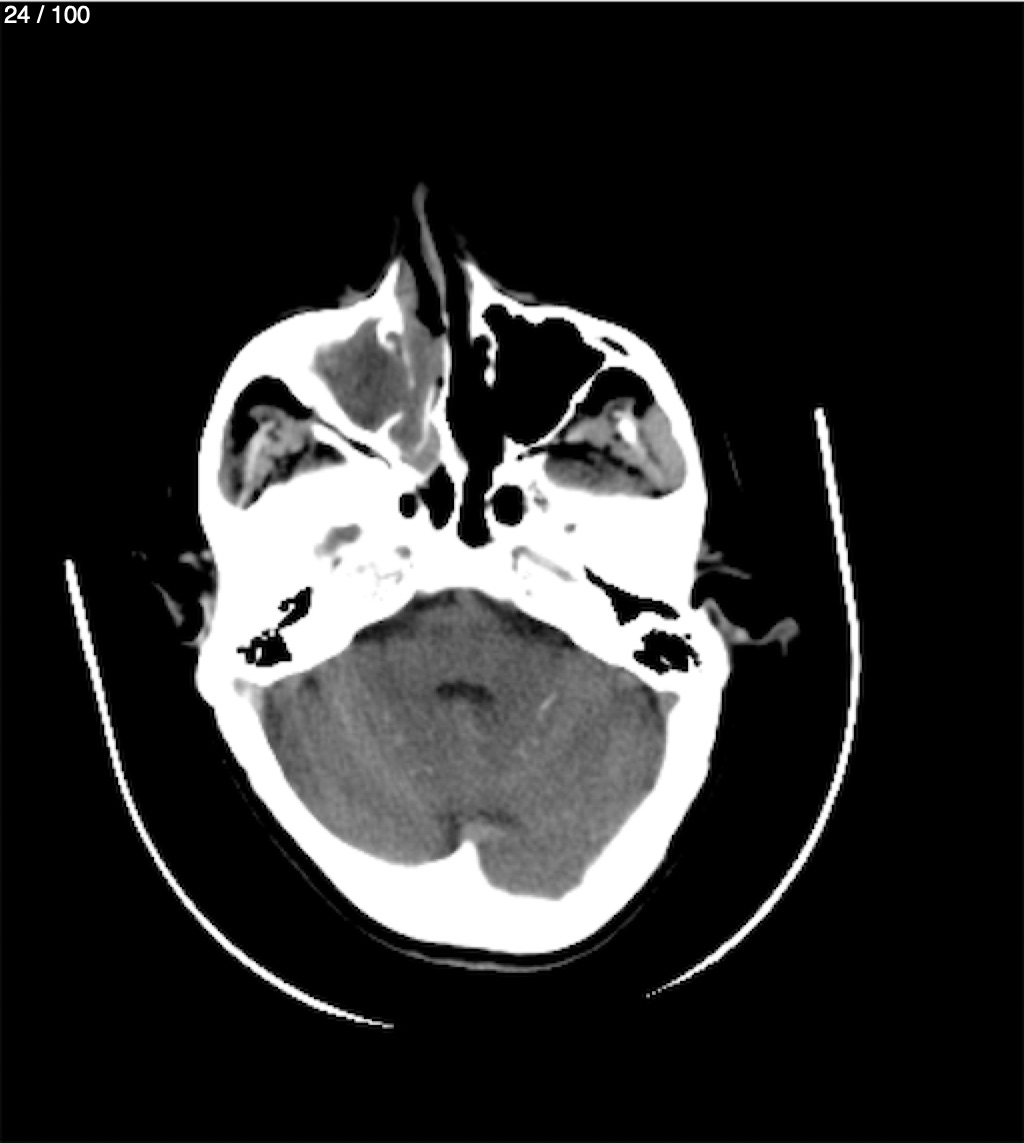

Valentin Perez Gomez 69A - T.C Craneo